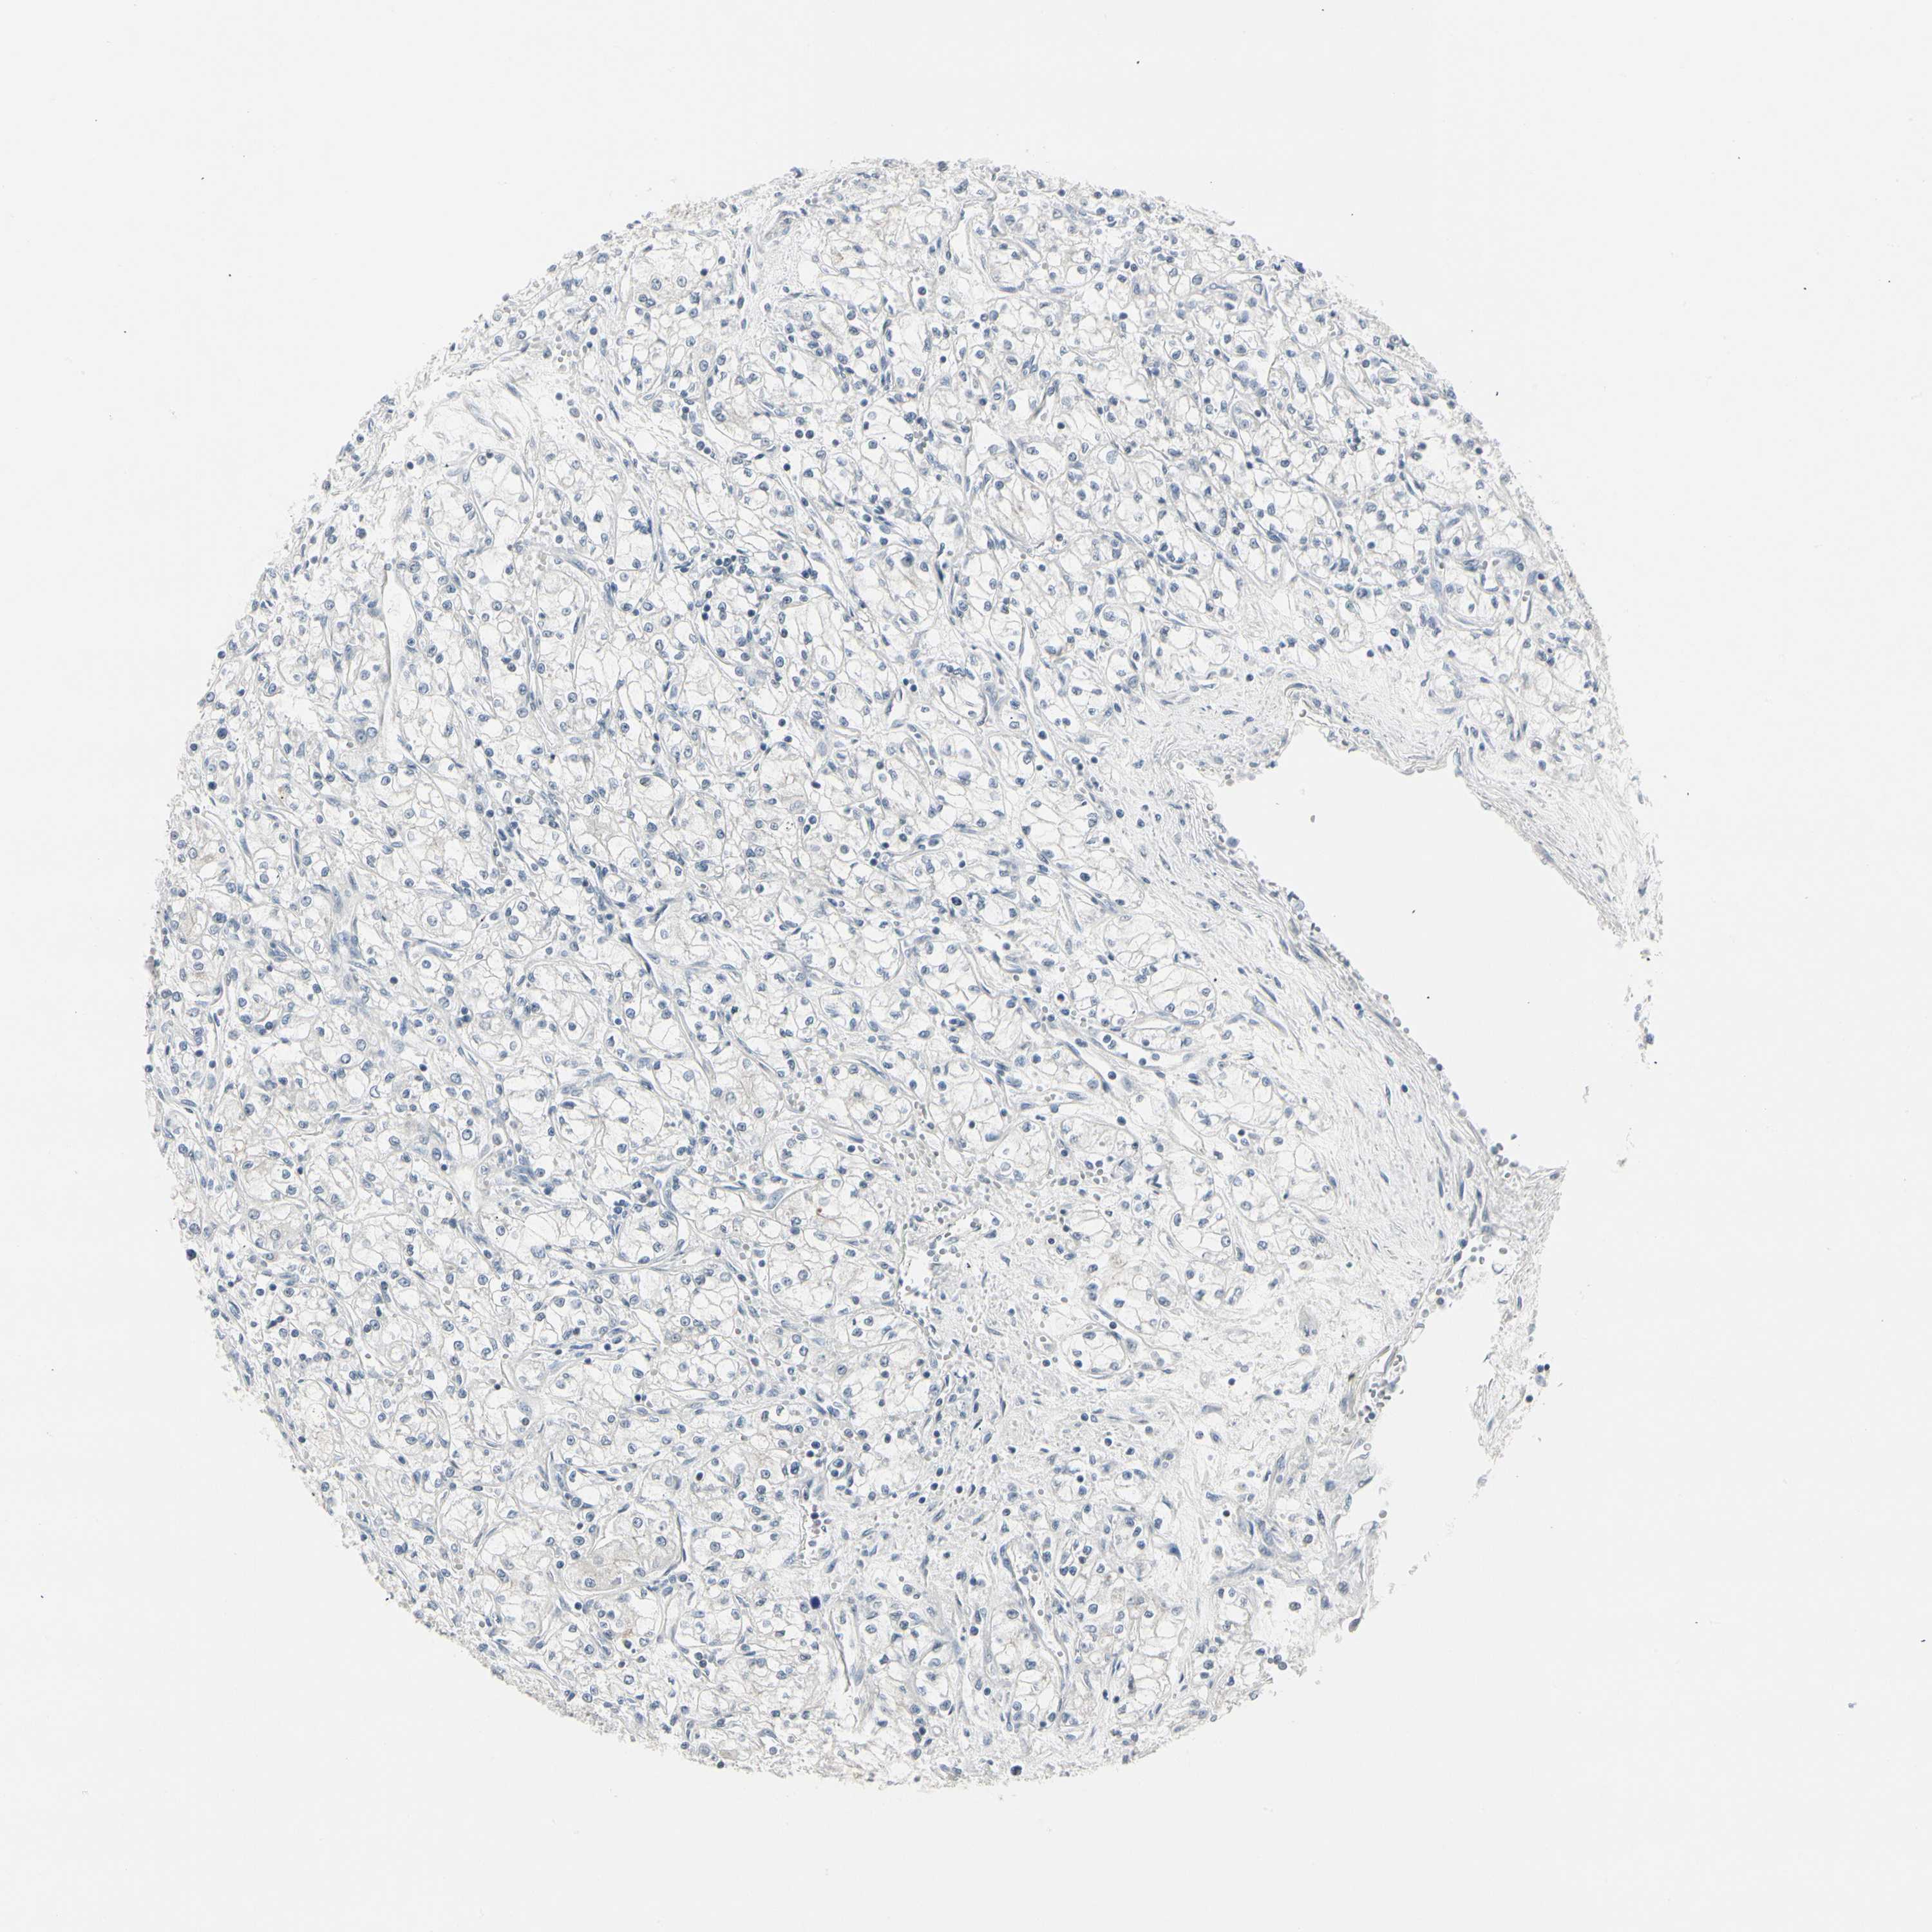

CANCER RENAL CANCER Show tissue menu

KICH TCGA KIRC TCGA KIRC VALIDATION KIRP TCGA PROTEIN RCC CPTAC PROTEIN EXPRESSION